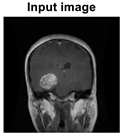

A method for enhancing the efficiency of a machine learning model is called data preprocessing, which involves purifying and preparing data for usage by the model. The skull photos in the MRI datasets are not all identical in width and height; instead, each image is scaled to 32 × 32 pixels for training purposes. The grayscale conversion of these data contributes to a reduction in the level of complexity. Digital images can be noise-free without having their edges blurred through the utilization of the anisotropic diffusion filter. After the utilization of the anisotropic diffusion filter, Table 1 represents the filtered dataset.

Figure 1. MRI scans performed on two different brains. (a) On the left is a tumor, and (b) on the right is a healthy brain [8].